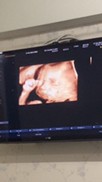

รูปซาวด์ตอน20W ค่ะ ก็อ้าปากโชว์ป้าหมอไปเลย ตอนนี้22W6Dแล้วค่ะ ผมเป็นเด็กผู้ชายครับ

ซาวด์ตอน 25w5dค่ะ น้ำหนักน้อง 990g ทีมชาย ค่ะ

ซาวด์ตอน 30w4d ค่ะ น้ำหนัก 1280g เด็กชาย ค่ะ

ซาวด์ตอน22+5วีคค้าบผม

17 วีคค่ะ #ทีม กรกฎาคม

21 สัปดาห์3วันค่ะ

ซาวด์ตอน19+2ค่ะ